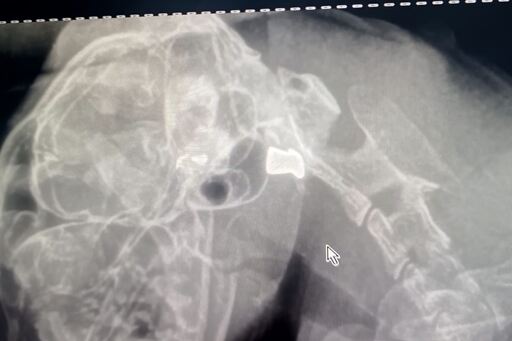

Após exames, foi constatado que o animal havia sido atingido por um tiro no ouvido, com o projétil ainda alojado.

- O veterinário informou que o projétil não poderia ser retirado, pois entrou pelo olho direito e ficou alojado no ouvido. Apesar da gravidade, o gato está se recuperando, já voltou a comer e aguarda uma nova consulta para avaliar possíveis tratamentos – diz a moradora.